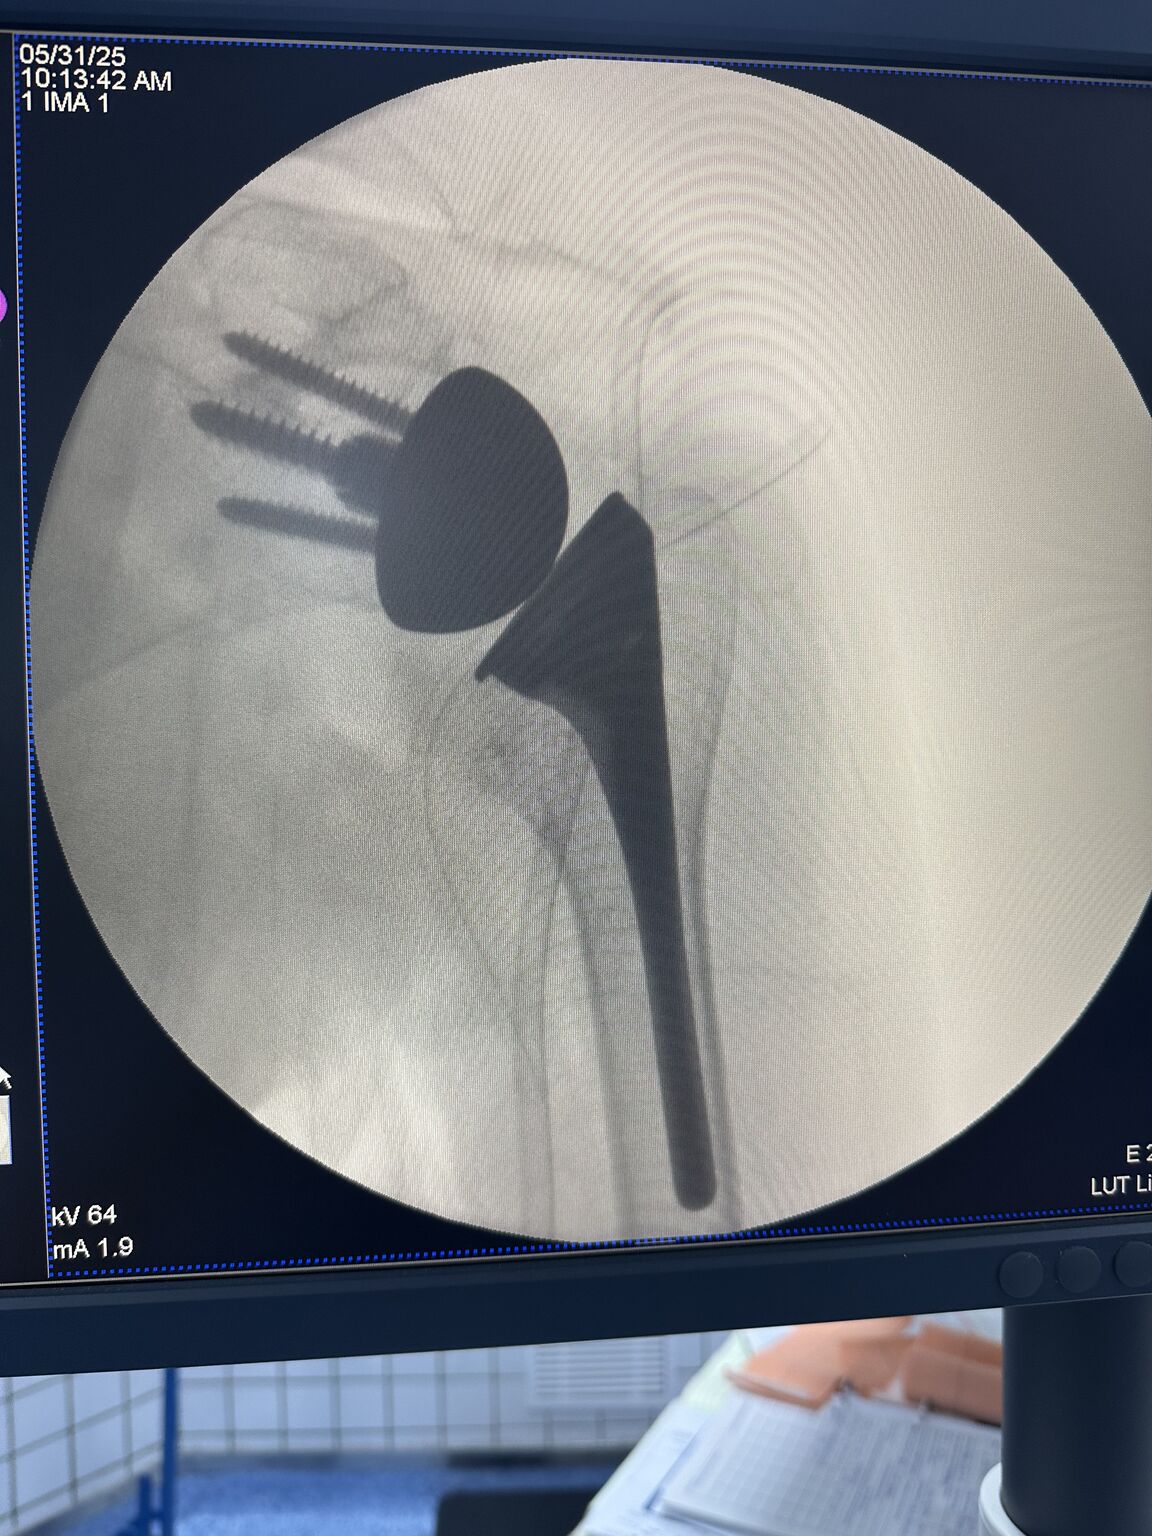

Reverse Shoulder Replacement

Had discussions on Arthroscopic Transosseous Repair, Reverse Shoulder Replacement, and Lower Trapezius Transfers. Explained our protocols and shared experiences. Had an engaging three days in our unit.

#Reverse Shoulder Replacement